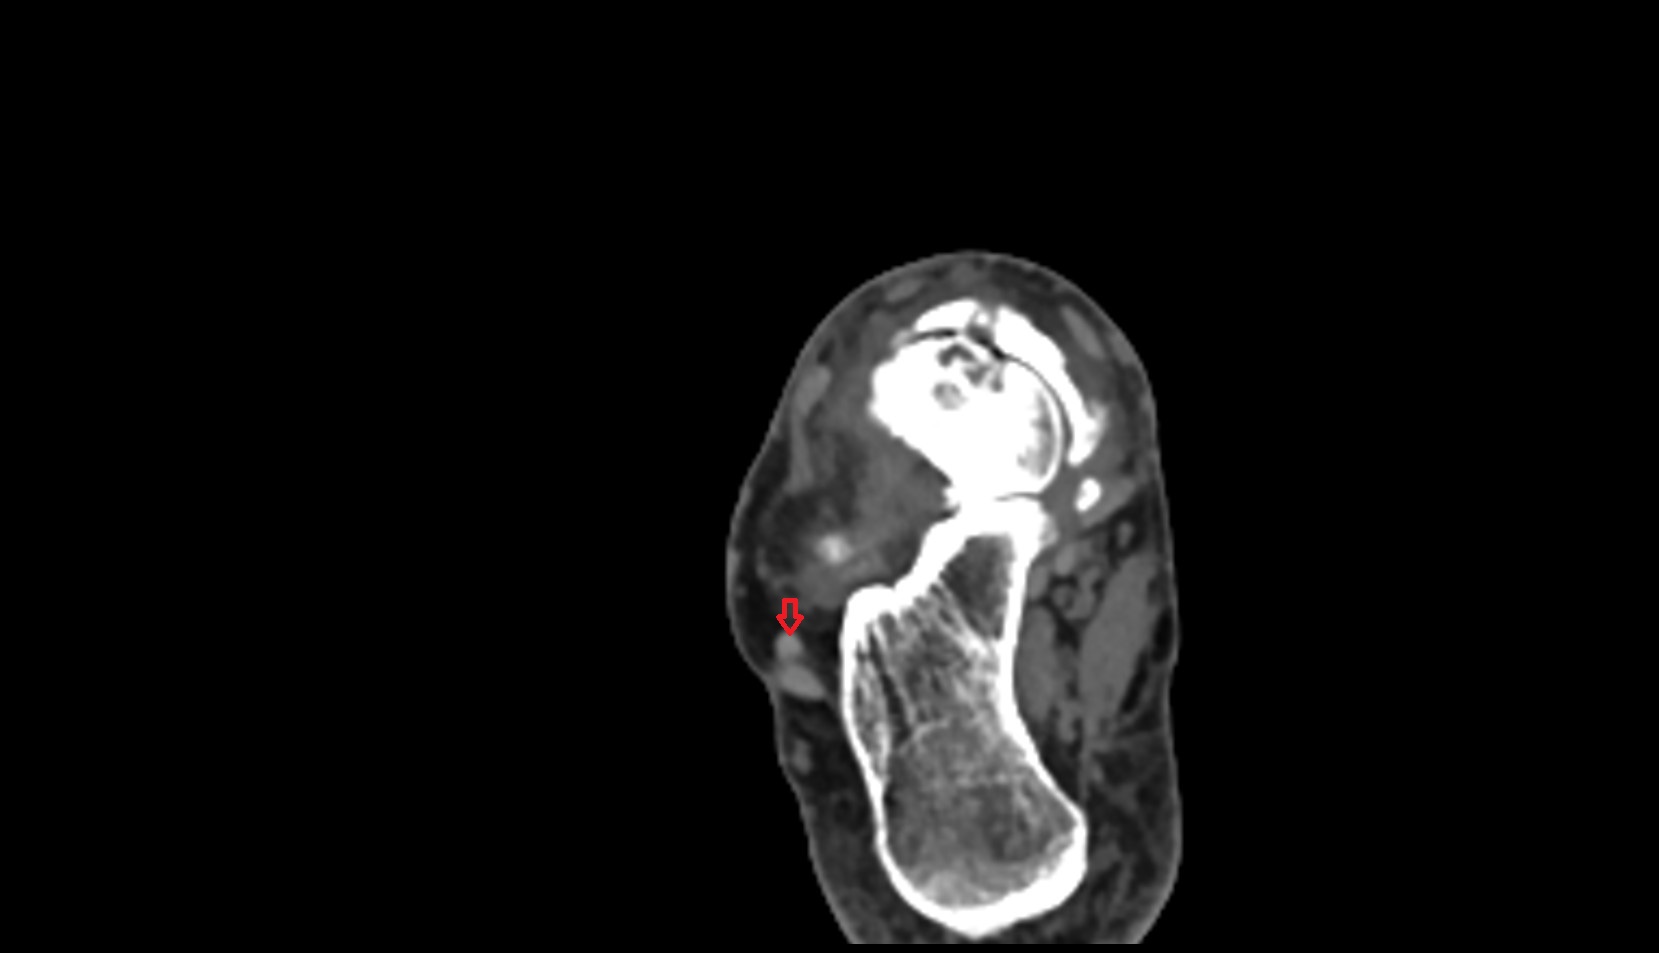

- Temporomandibular joint

- Mandibular condyle

- Mandibular fossa

- Articular disc of temporomandibular joint

- Articular eminence

- Articular surface of mandibular fossa